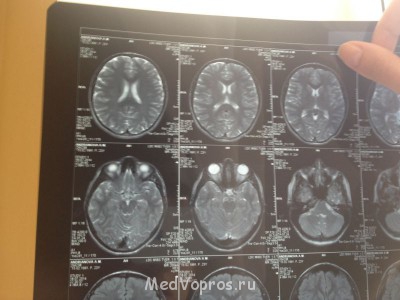

Вот фото

Наружная заместительная гидроцефалия